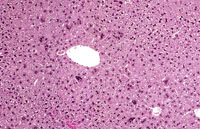

Adult mouse liver with scattered multinucleated hepatocytes

A mouse treated chronically with chlordane, showing enlarged hepatocytes with multiple nuclei.